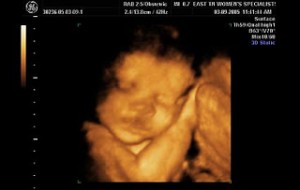

Bebeğin Boyutu: 43.7 cm, 1.9 kg

Hamileliğin (Gebeliğin) 35. Haftası Resim ve Video;